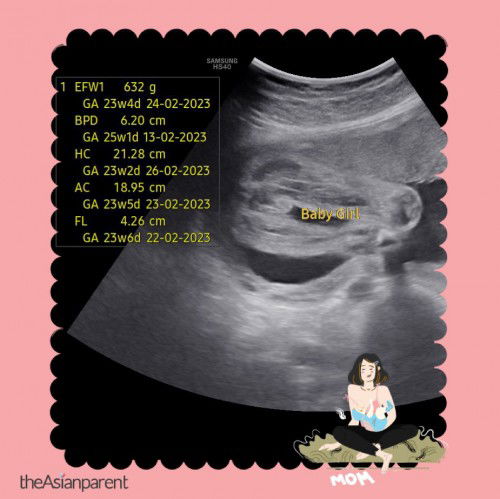

Tolong mummy…doc cakap girl tp tak pasti …ada mummy2 pandai tengok tak,,confirm ke girl?? 24weeks…thankyou♥️

Girl. Sbb ada line kat tgh

Girl ni.